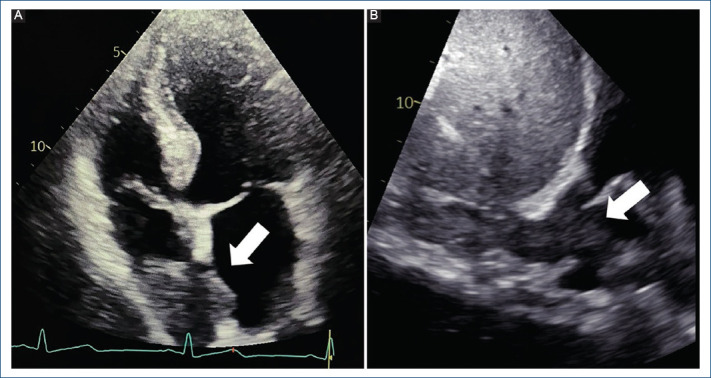

Hepatocellular carcinoma with inferior vena cava tumor thrombus extending into cardiac chambers: case report.